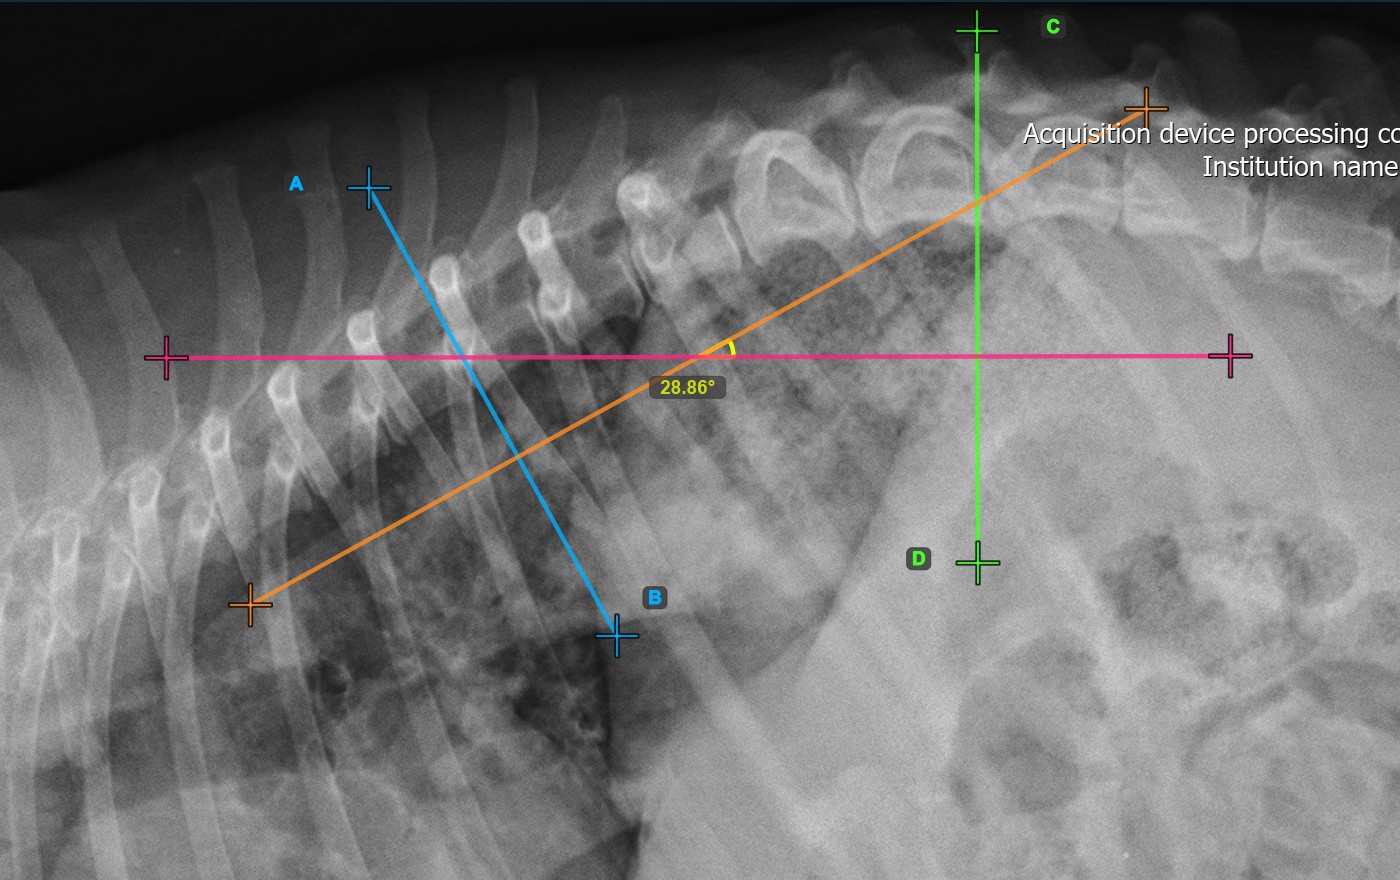

Das untenstehende Bild zeigt eine typische Platzierung der zweiten Wirbellinie.

../../_images/image374.jpg